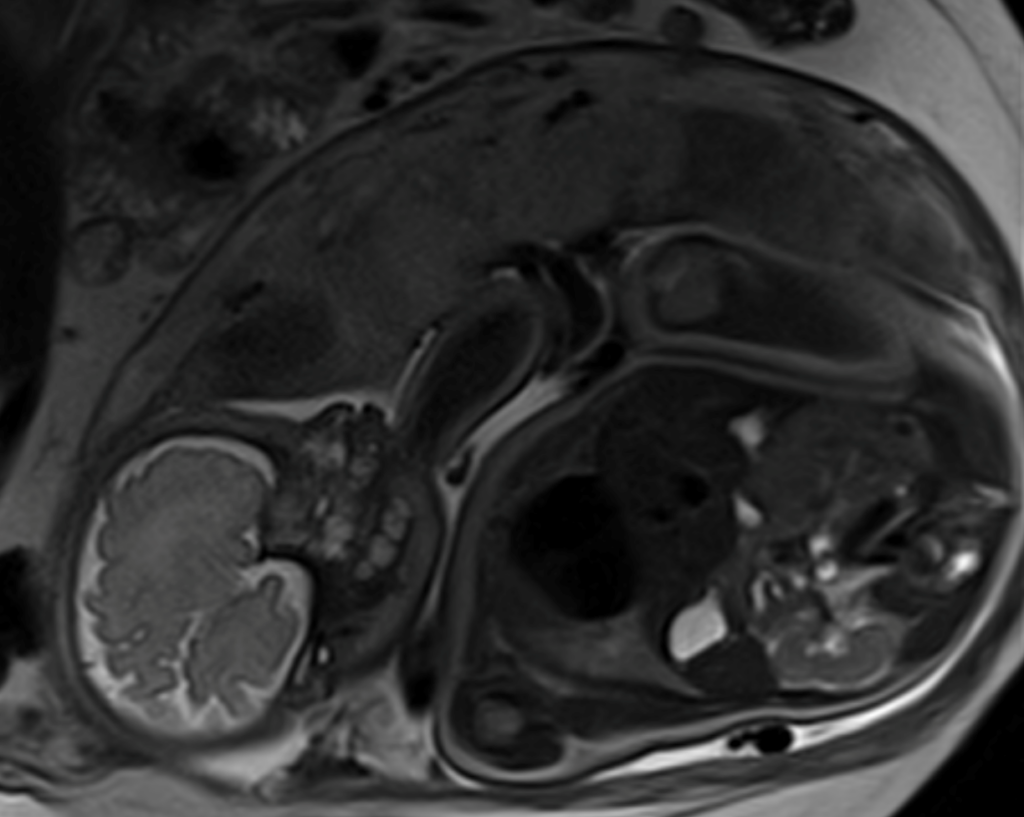

- Be given a framed set of your baby’s MRI images, taken at each study visit as they grow (see example image below).